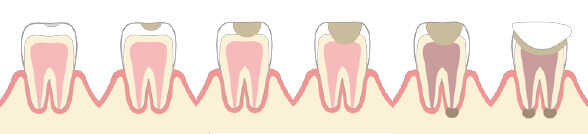

歯のライフサイクル

歯は、何度でも治療できるわけではありません。

虫歯になる度に歯はどんどん削られ、最終的に抜歯になります。